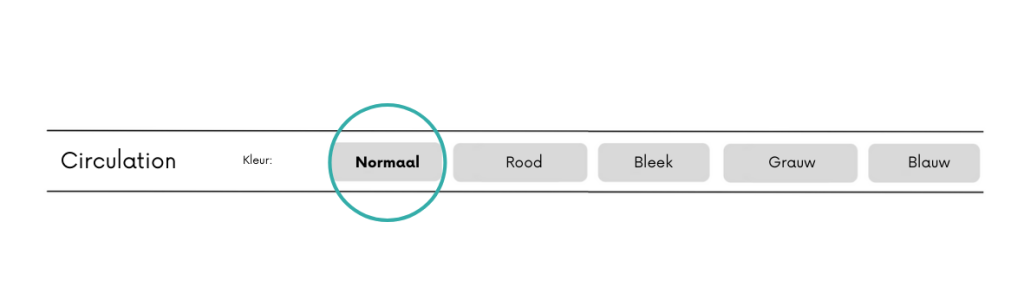

Tijdens triage is het belangrijk om te weten of de kleur van de huid veranderd is.

- Is er iets veranderd aan de kleur van het gelaat?

- Is de kleur van het gezicht anders dan normaal?

Denk na over de vraagstelling. Wat is uw huidskleur is geen gepaste vraag. Dit kan als racistisch worden opgevat! Het gaat erom of de huid anders eruit ziet dan normaal. En zo ja, vraag het volledige toestandsbeeld uit om te kunnen bepalen of het een circulair probleem is.

Is de kleur van de huid niet veranderd scoor je op normaal. Rood valt ook nog onder normaal. Wanneer iemand bleek ziet is het belangrijk om na te denken over de oorzaak van het bleek zien. Iemand die ziek is ziet veelal bleek. Is iemand bleek na een trauma denk dat na over inwendige en uitwendige bloedingen. Is er veel bloed verloren uitwendig? Denk dat na of er ook inwendig letsel kan zijn!

Iemand die grauw of blauw ziet kan een groot circulair probleem hebben, er is te weinig zuurstofrijk bloed wat circuleert. Vraag direct door. Is er sprake van bijvoorbeeld pijn op de borst? Erge hoofdpijn? Een trauma? Is de patiënt duizelig? Is de patiënt misselijk? Is de patiënt aan het zweten?